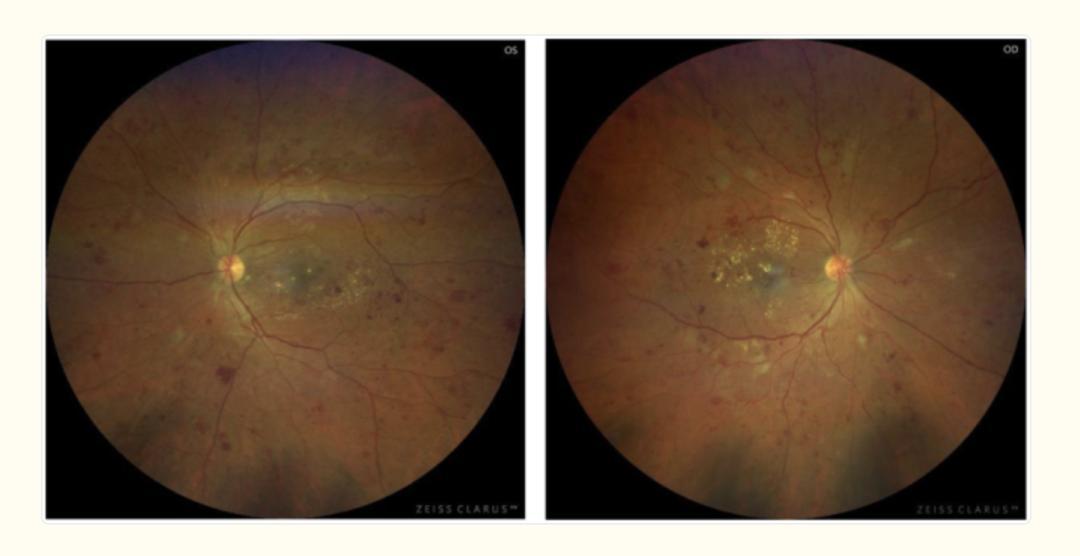

《PMC》的一篇病例報告中,報道過一位 33 歲男性患者,視力在短短一週內,從正常退化到只能看得到手指晃動。

醫生通過眼底鏡一看:視網膜上佈滿了出血點和滲出物,中心黃斑區可見水腫。

圖片來源:文獻

高血糖環境下,微血管可能受氧化應激和炎症影響,變得脆弱易滲漏。爲了代償,眼底可能出現視網膜微血管瘤及生成新生血管,但這些血管易破裂導致出血。

這是典型的糖尿病視網膜病變(DR)。